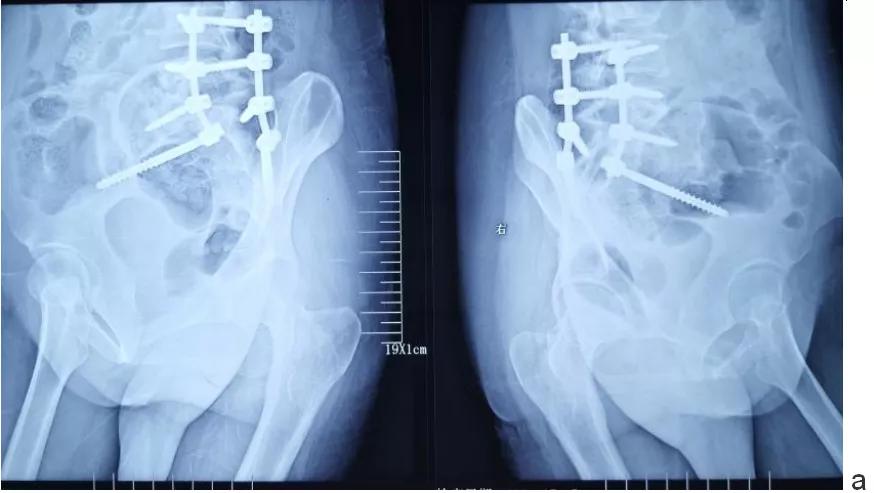

术后影像学检查

c.前路植骨术后正侧位片示腰4/5/骶1螺钉位置良好,腰5-骶1椎间植骨(自体髂骨三层皮质骨)位置良好。